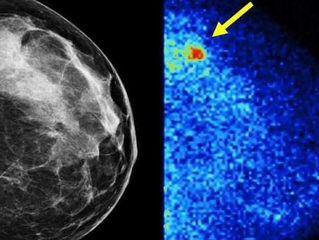

Mayo doctors in La Crosse call breast cancer screening tool an early success

Doctors at Mayo-Franciscan in La Crosse say a new, cutting-edge breast cancer screening tool is already paying major dividends. Mayo is...